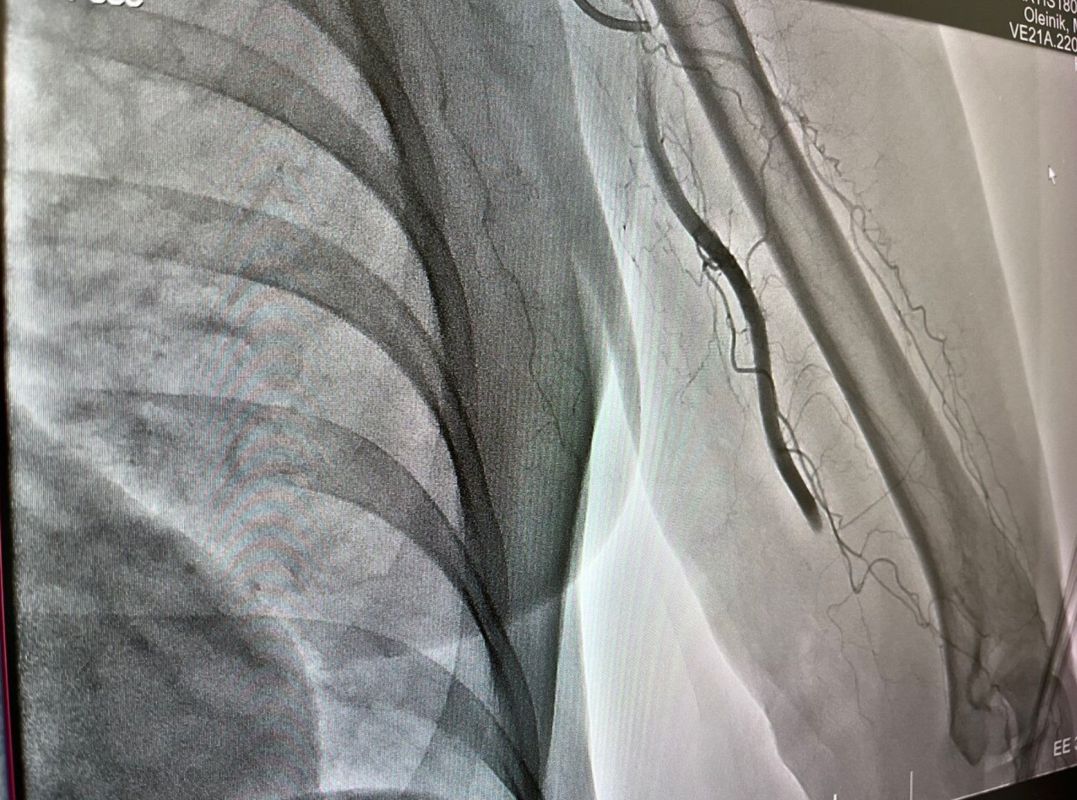

Как сообщил министр здравоохранения Кузбасса Андрей Тарасов, в Новокузнецкой городской клинической больнице №1 имени Г.П. Курбатова из плечевой артерии левой руки женщины был извлечен 7-сантиметровый тромб.

Специалисты провели процедуру тромбэкстракции, введя микрокатетер через бедренную артерию. Им удалось достичь места закупорки и успешно удалить тромб. В результате кровоснабжение было восстановлено, и состояние пациентки стабилизировалось. Жизнь и здоровье женщины теперь вне опасности.